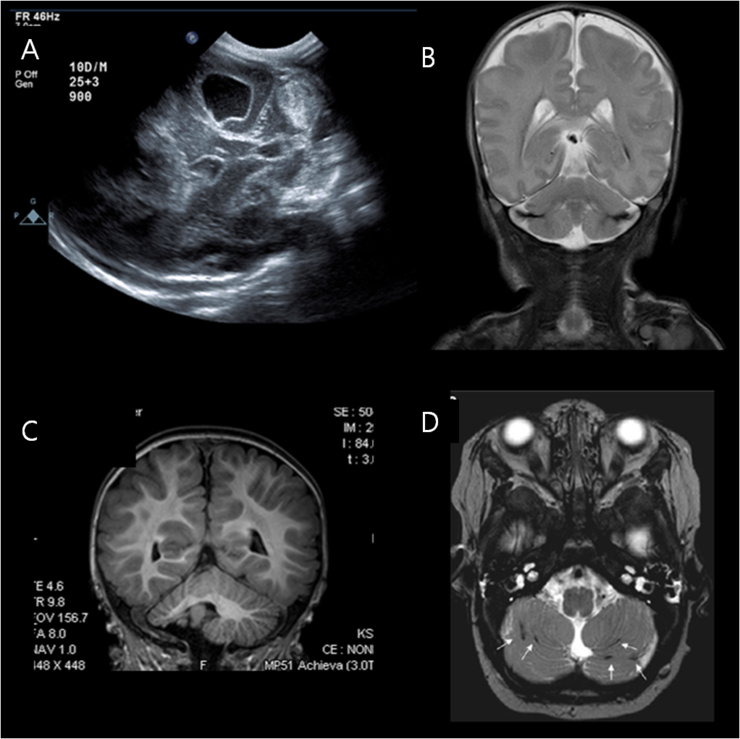

피검사 후 쉴 틈도 없이 뇌 초음파를 찍으러 갔다. 자연분만에서 태어난 아기는 미세한 뇌출혈이 생긴다고 한다. 산도를 벗어나면서 머리가 눌리기 때문에 생기는데 자연스럽게 흡수되면 괜찮지만 그렇지 않으면 문제가 된다고 한다. 소리도 경미한 뇌출혈이 있어 잘 흡수되는지 확인하기 위해 뇌 초음파를 찍으러 갔다. 대학병원이지만 신생아 검사는 빨리 진행하려는 듯해 모든 검사를 긴 대기 없이 할 수 있었다. 머리에 치약을 짜듯 젤을 바른 뒤 뇌 초음파를 보는 데 10분 정도 걸린 것 같다. 처음에는 잘 참아주고 또 울기 시작한다. 머리는 촉촉하게 젖고, 또 나를 도와줘, 빼르륵. 1시간 30분 전에 밥을 먹고 출발해서 그런지 모르겠다.

차에서 대기하다가 소아과 예약시간에 맞춰 다시 진료실로 갔다. 피곤하다. 다행히 검사결과는 피검사(갑상선 수치) 이상 없음.뇌 초음파 이상 없음. 건강하게 체중도 800g이나 늘어서 선생님이 아기 잘 먹나봐요~라는 말도 들었다. 소아과 진료를 보면서 우리가 걱정했던 황달 이야기도 했다. 모유 수유를 일주일 동안 끊었는데도 좀처럼 빠지지 않는다고 했더니 모유를 너무 오랫동안 끊었다며 황달 검사를 했고, 어떻게 분유와 모유를 어떻게 할지 결과를 물어보라고 해서 서둘러 황달 검사를 하러 갔다. 다행히 배 밑에 황달이 진행되지 않아 걱정은 없다고 하셨는데 정확히 검사를 하기로 했다.